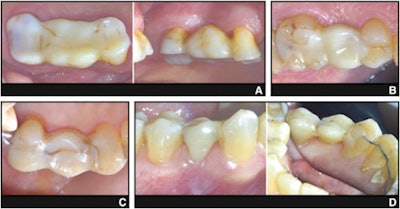

Representative photographs of four different directly fiber-reinforced composite fixed partial dentures (DFRC-FPD). (A) DFRC-FPD replacing left maxillary second premolar, supported by first premolar and first molar; in function for 13 years. Fiber bundles partially visible, but restoration clinically intact. (B) DFRC-FPD replacing left maxillary first molar, supported by second premolar and second molar; in function for 12 years, without clinical signs of failure. (C) DFRC-FPD replacing left maxillary second premolar, supported by canine and first molar; showing unilateral fracture after six years, likely associated with occlusal overload and shearing forces. (D) DFRC-FPD replacing right mandibular second premolar, supported by first premolar and first molar; showing bilateral fracture after nine years, attributed to accidental occluding on olive pit. DFRC-FPD, direct fiber-reinforced composite fixed partial denture.Image and caption courtesy of Roccuzzo et al. Licensed under CC BY 4.0.